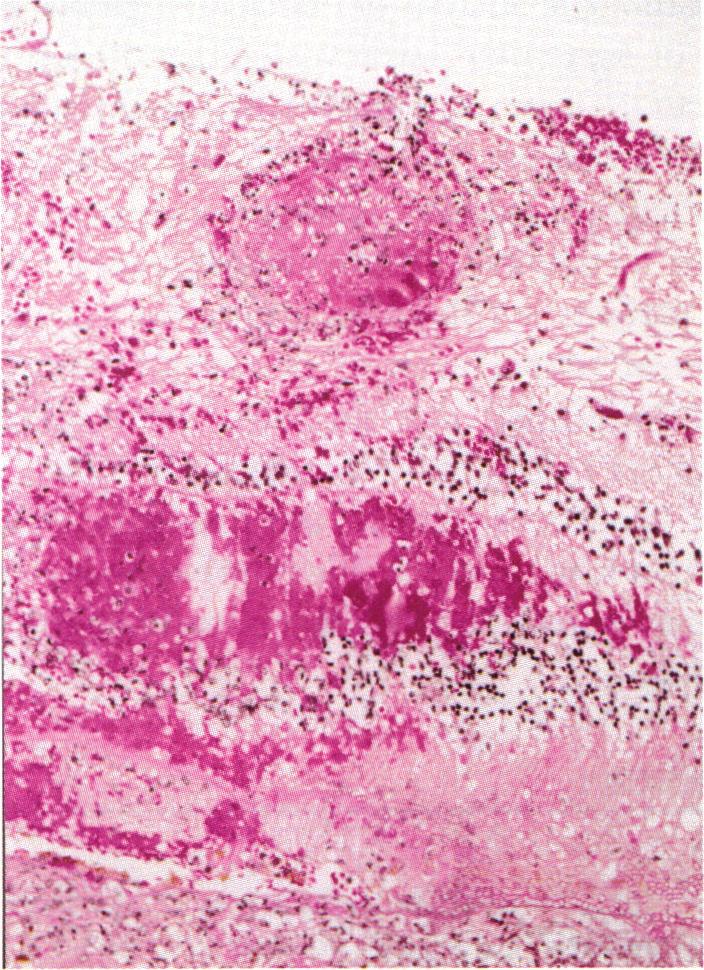

Endophthalmitis caused by endogenous Candida and Aspergillus species has emerged as a visually threatening complication in patients with immune deficiency of various causes. Twenty-five patients who underwent enucleation, 13 with endogenous Aspergillus endophthalmitis and 12 with endogenous Candida intraocular infections, were evaluated. Both clinical features and intraocular spread of the fungi were studied to determine which clinical and/or histopathologic features could help distinguish aspergillosis from Candida infections.

Clinical information was sought from each case to determine whether there was any underlying systemic condition and to delineate the characteristic clinical features seen at initial presentation. The results of vitreous and other tissue cultures for bacteria and fungi were evaluated. Patients with AIDS were excluded. The enucleated globes were processed for histopathologic analysis to detect location of the fungal elements, inflammatory response, and vascular invasion by the fungi.

RESULTS

With respect to the various predisposing systemic conditions, Candida species endophthalmitis was noted in patients with a history of gastrointestinal surgery, hyperalimentation, or diabetes mellitus, whereas aspergillosis was present in patients who had undergone organ transplantation or cardiac surgery. The vitreous was the primary focus of infection for Candida, whereas subretinal or sub-retinal pigment epithelium infection was noted in eyes with aspergillosis. Retinal and choroidal vessel wall invasion by fungal elements was noted in cases of aspergillosis but not in cases with candidiasis. The high rate of cerebral and cardiac infection in patients with Aspergillus endophthalmitis was not seen in those with Candida infection.

CONCLUSIONS

The present study indicates that unlike Candida endophthalmitis, aspergillosis is seen in organ transplant or cardiac surgery patients, and its initial clinical presentation includes extensive areas of deep retinitis/choroiditis. Contrary to the findings in Candida endophthalmitis, vitreous biopsy may not yield positive results in aspergillosis. Aspergillus endophthalmitis is usually associated with a high rate of mortality caused by cerebral and cardiac complications.